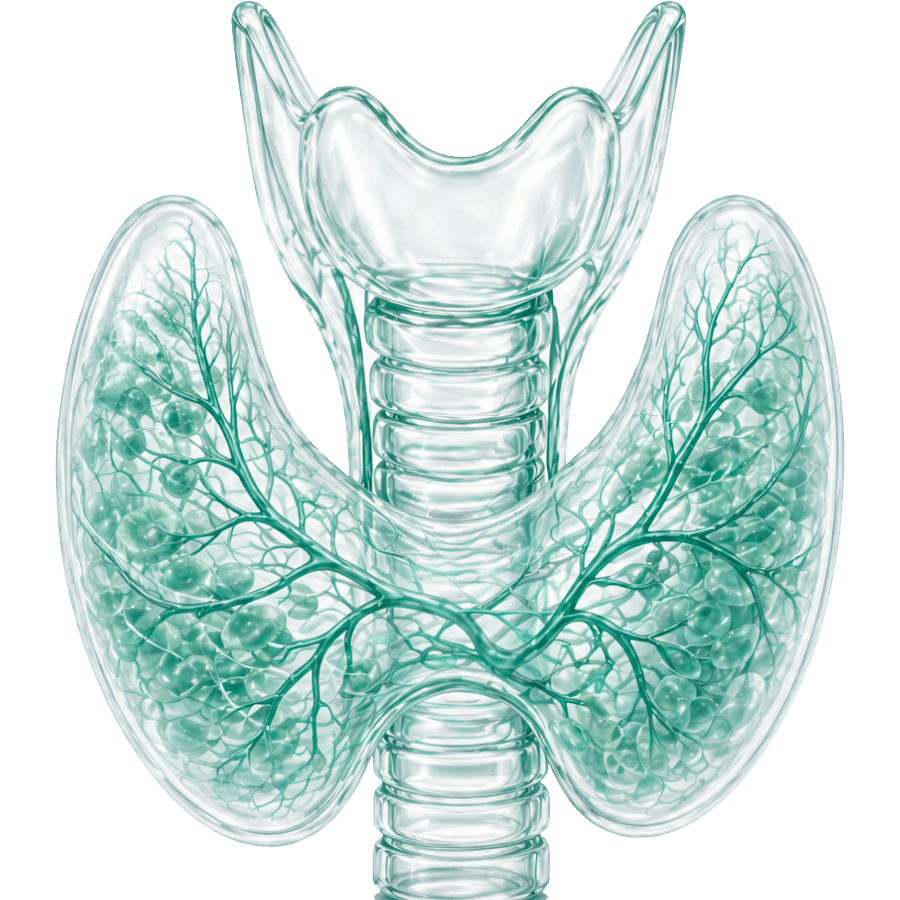

Эндокринология

қызметтер: 4